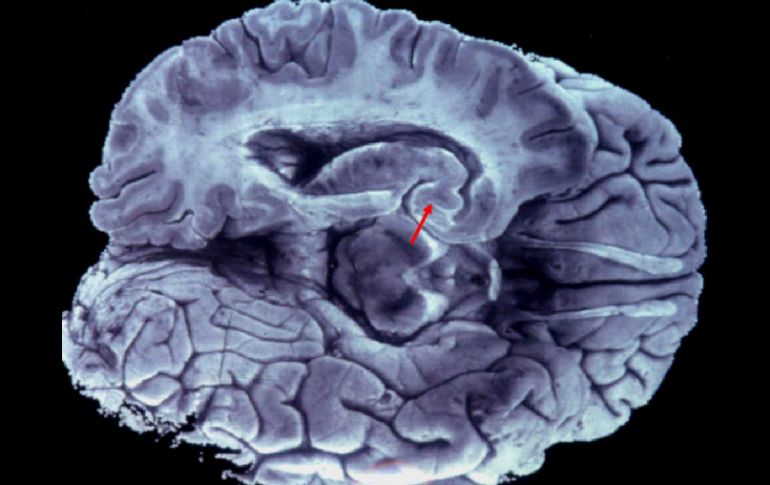

Es necesario mantener la reserva energética adecuada para el buen funcionamiento del órgano. EFE / ARCHIVO

Agregó que por esa razón es necesario mantener la reserva energética adecuada para resolver el problema.